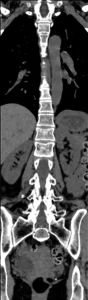

Tomografia Computada

TC ventanas de partes blandas y óseas. MPR en planos coronal y sagital. Permite caracterizar mejor la fractura, confirmar la protrusión del muro posterior hacia el canal. Descartar hematomas epidural y paravertebral.

Qué agrega la TC (y qué reportar):

- Define la morfología de la fractura (compresión vs estallido) y el grado de conminución.

- Evalúa el muro posterior y la posible retropulsión hacia el canal.

- Valora compromiso de arcos posteriores (pedículos, láminas, apófisis espinosas/transversas).

- Permite medir de forma más confiable la pérdida de altura y la angulación.